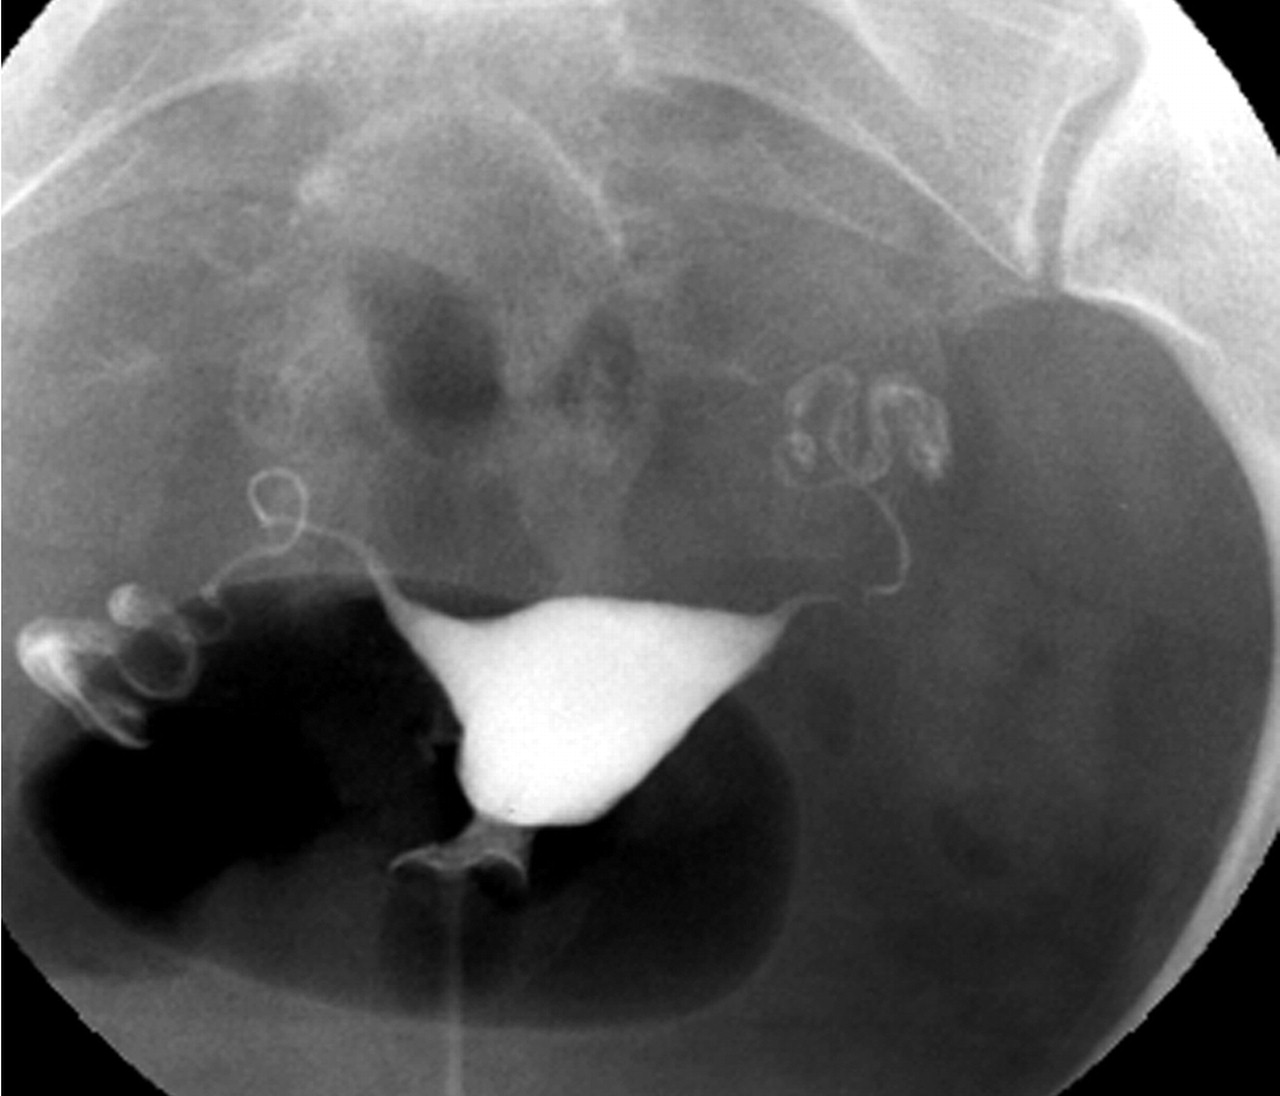

사진을 보면 더 정확하게 알 수 있습니다.

사진을 보시면 자궁경부 입구  주사기 안에 들어 있는 조영제를 순차적으로 점점 밀어 넣게 됩니다.

그래서 만일 나팔관이 막혀 있지 않다면 자궁안을 채우고 난 이후 나팔관으로 순차적으로 조영제가 빠져 나가는 것이 확인이 되겠지만, 만일 자궁에 혹이 있는 경우엔 그 부분이 검게 뚫어져 있을 것이고, 나팔관이 막혀 있다면 나팔관 바깥쪽으로 조영제가 빠져 나가질 않을 것입니다.